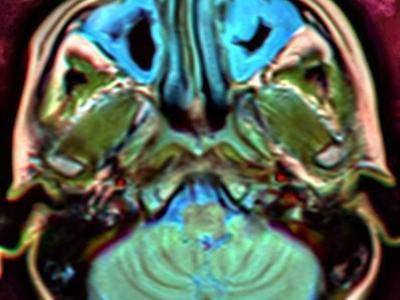

Hip replacement outcomes are not linked to OA severity, instead pts muscle quality before THA best predicts recovery after surgery. Imaging of 10 pts undergoing THA showed poor muscle quality predicted post-op performance/movement after surgery https://t.co/io0UXQl6n2 https://t.co/cFM7Fg10Zm